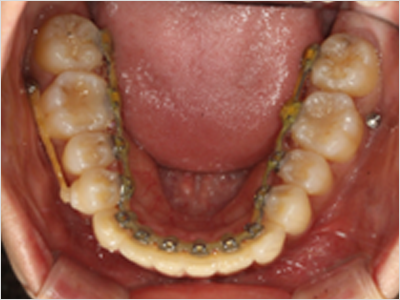

LINGUAL ORTHODONTICS

안보이게 아름답게

설측교정

설측교정은 치아 안쪽(설측면)에 초소형 장치로 보이지 않게

아름다운 미소를 만드는 고난이도 프리미엄 교정 치료입니다.

3D 디지털 기술을 활용한 맞춤 설계, IDBS방식을 통한

정밀하고 불편감 없는 치료를 제공합니다.

콤비교정

상악

교정장치를 안쪽에 부착

하악

교정장치를 바깥쪽에 부착